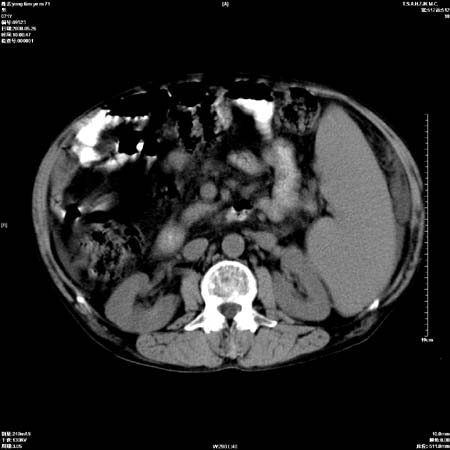

以下是引用医影拾贝在2008-6-5 22:48:00的发言:[br]肝硬化、门脉高压、胃底食管静脉曲张、低蛋白血症(胆囊壁水肿、增厚)、腹水[br]脾功能亢进、脾大、脾、左肾囊肿[br]肝囊性占位、不除外肝脓肿可能[br]建议增强以除外肝右叶肝ca可能

以下是引用chenglinhunan在2008-6-5 22:53:00的发言:[br]1. 肝硬化腹水,脾肿大。[br]2. 肝右后叶占位,肝癌。[br]3。建议ct增强扫描。

以下是引用xulianj在2008-6-5 21:40:00的发言:[br]支持肝硬化腹水;建议增强。肝、脾、肾囊肿待排。

以下是引用zjzjr在2008-6-6 12:34:00的发言:[br]1. 肝硬化腹水,脾肿大。[br]2. 肝右后叶占位,肝癌。[br]3。建议ct增强扫描。[br]4肝脾囊肿.